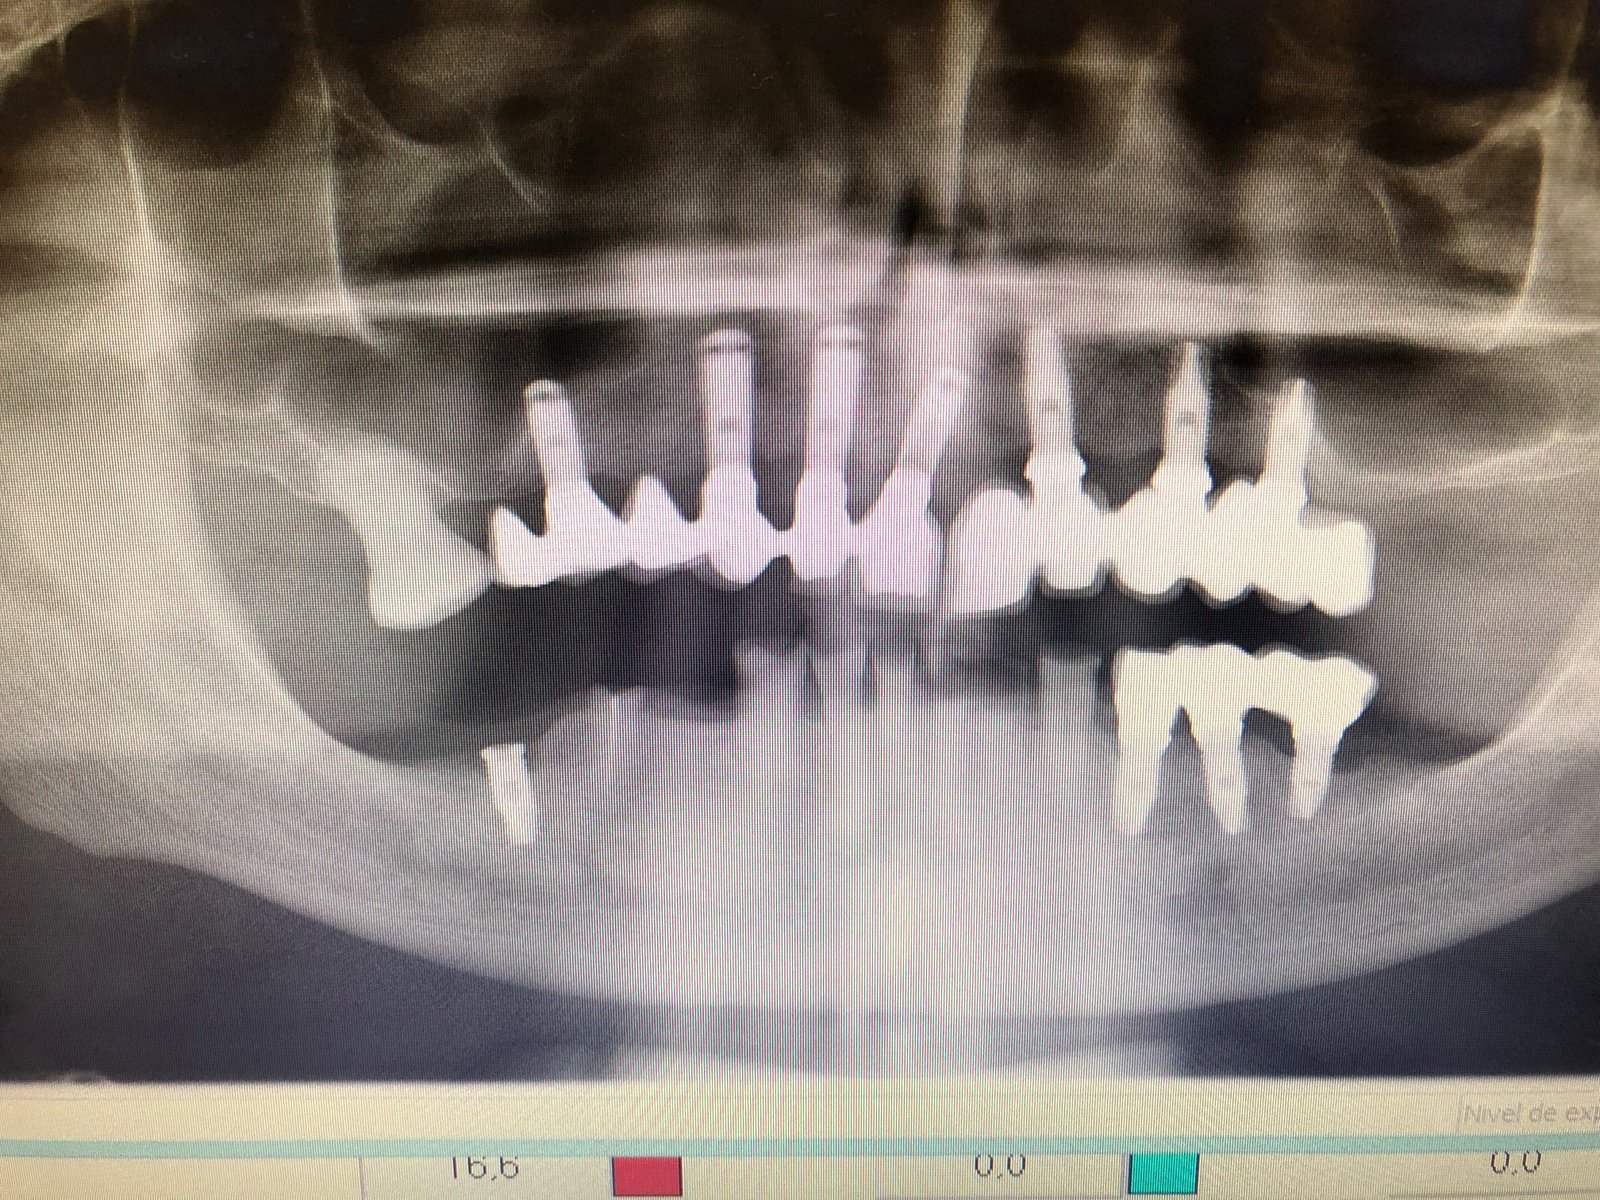

Buenas, tengo este caso que quiere ponerse una prótesis completa usando los implantes antiguos. Por desgracia no tengo ni idea de qué tipo de implantes se trata. A simple vista [...]